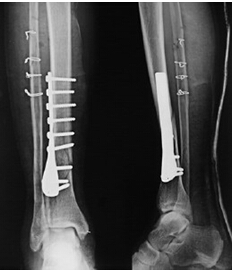

骨折現(xiàn)象多見(jiàn)于兒童及老年人,中青年也時(shí)有發(fā)生,患上骨折嚴(yán)重的影響生活和學(xué)習(xí)及工作,所以我們要了解骨折的癥狀,下面就為大家介紹一下骨折的癥狀有哪些?

二局部表現(xiàn):骨折的局部表現(xiàn)包括骨折的專(zhuān)有體征和其他表現(xiàn)。

(1)畸形:骨折段移位可使患肢外形發(fā)生改變主要表現(xiàn)為縮短;